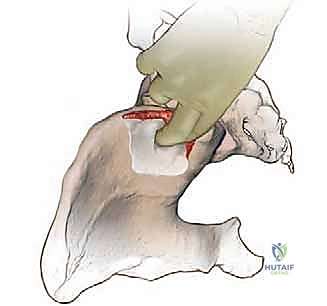

2. التشريح الخلفي لحرقفة الحوض (Posterior Iliac Crest)

يُعد الجزء الخلفي من الحرقفة هو الموقع الأكثر شيوعاً واستخداماً لأخذ الطعوم العظمية، خاصة في جراحات دمج الفقرات القطنية والصدرية حيث يكون المريض مستلقياً على بطنه (Prone). يتميز هذا الموقع بأنه يوفر كميات هائلة من العظم الإسفنجي عالي الجودة، بالإضافة إلى إمكانية أخذ طعوم قشرية كبيرة.

- المعالم العظمية الرئيسية: النقطة البارزة هنا هي الشوكة الحرقفية الخلفية العلوية (PSIS)، والتي تظهر غالباً كغمازة أسفل الظهر فوق الأرداف. المنطقة الممتدة للأمام وللخارج من هذه الشوكة هي بنك عظمي ممتاز.

- المخاطر العصبية والوعائية الدقيقة:

- الأعصاب الألوية العلوية (Superior Cluneal Nerves): هذه الأعصاب مسؤولة عن الإحساس في الجلد فوق الأرداف. تعبر هذه الأعصاب حافة الحوض على مسافة تتراوح بين 6 إلى 8 سنتيمترات بعيداً عن خط الوسط لجسم الإنسان. لتجنب قطع هذه الأعصاب (والذي يسبب تنميلاً مزمناً أو ألماً عصبياً في الأرداف)، يحرص الأستاذ الدكتور محمد هطيف على ألا يتجاوز الشق الجراحي واستخراج العظم مسافة 8 سم من الشوكة الحرقفية الخلفية العلوية.

- الثقبة الوركية الكبرى (Greater Sciatic Notch): تقع أسفل الشوكة الحرقفية الخلفية. يمر عبرها العصب الوركي (Sciatic Nerve) والشريان الألوي العلوي (Superior Gluteal Artery). النزول بعمق كبير أثناء أخذ العظم قد يهدد هذه الهياكل الحيوية، مما قد يسبب نزيفاً حاداً يصعب السيطرة عليه أو إصابة عصبية كارثية. لذلك، يتم أخذ العظم دائماً من المنطقة العلوية الآمنة.

الخطوات الجراحية التفصيلية لأخذ الطعم العظمي: دقة متناهية

تُجرى هذه العملية تحت التخدير العام. وتختلف الخطوات بناءً على ما إذا كان الطعم سيؤخذ من الجزء الأمامي أو الخلفي للحوض. سنستعرض هنا الخطوات القياسية التي يتبعها الأستاذ الدكتور محمد هطيف لضمان أعلى درجات الأمان واستخراج أفضل جودة من العظم.

أولاً: التخطيط وتحديد موقع الشق الجراحي

يتم تحديد المعالم العظمية (مثل الشوكة الحرقفية) بدقة باستخدام الجس. يتم رسم خط الشق الجراحي بحيث يكون تجميلياً قدر الإمكان، وغالباً ما يُخفى في خطوط الجلد الطبيعية أو تحت خط الملابس الداخلية. في الحوض الخلفي، يتم التأكد